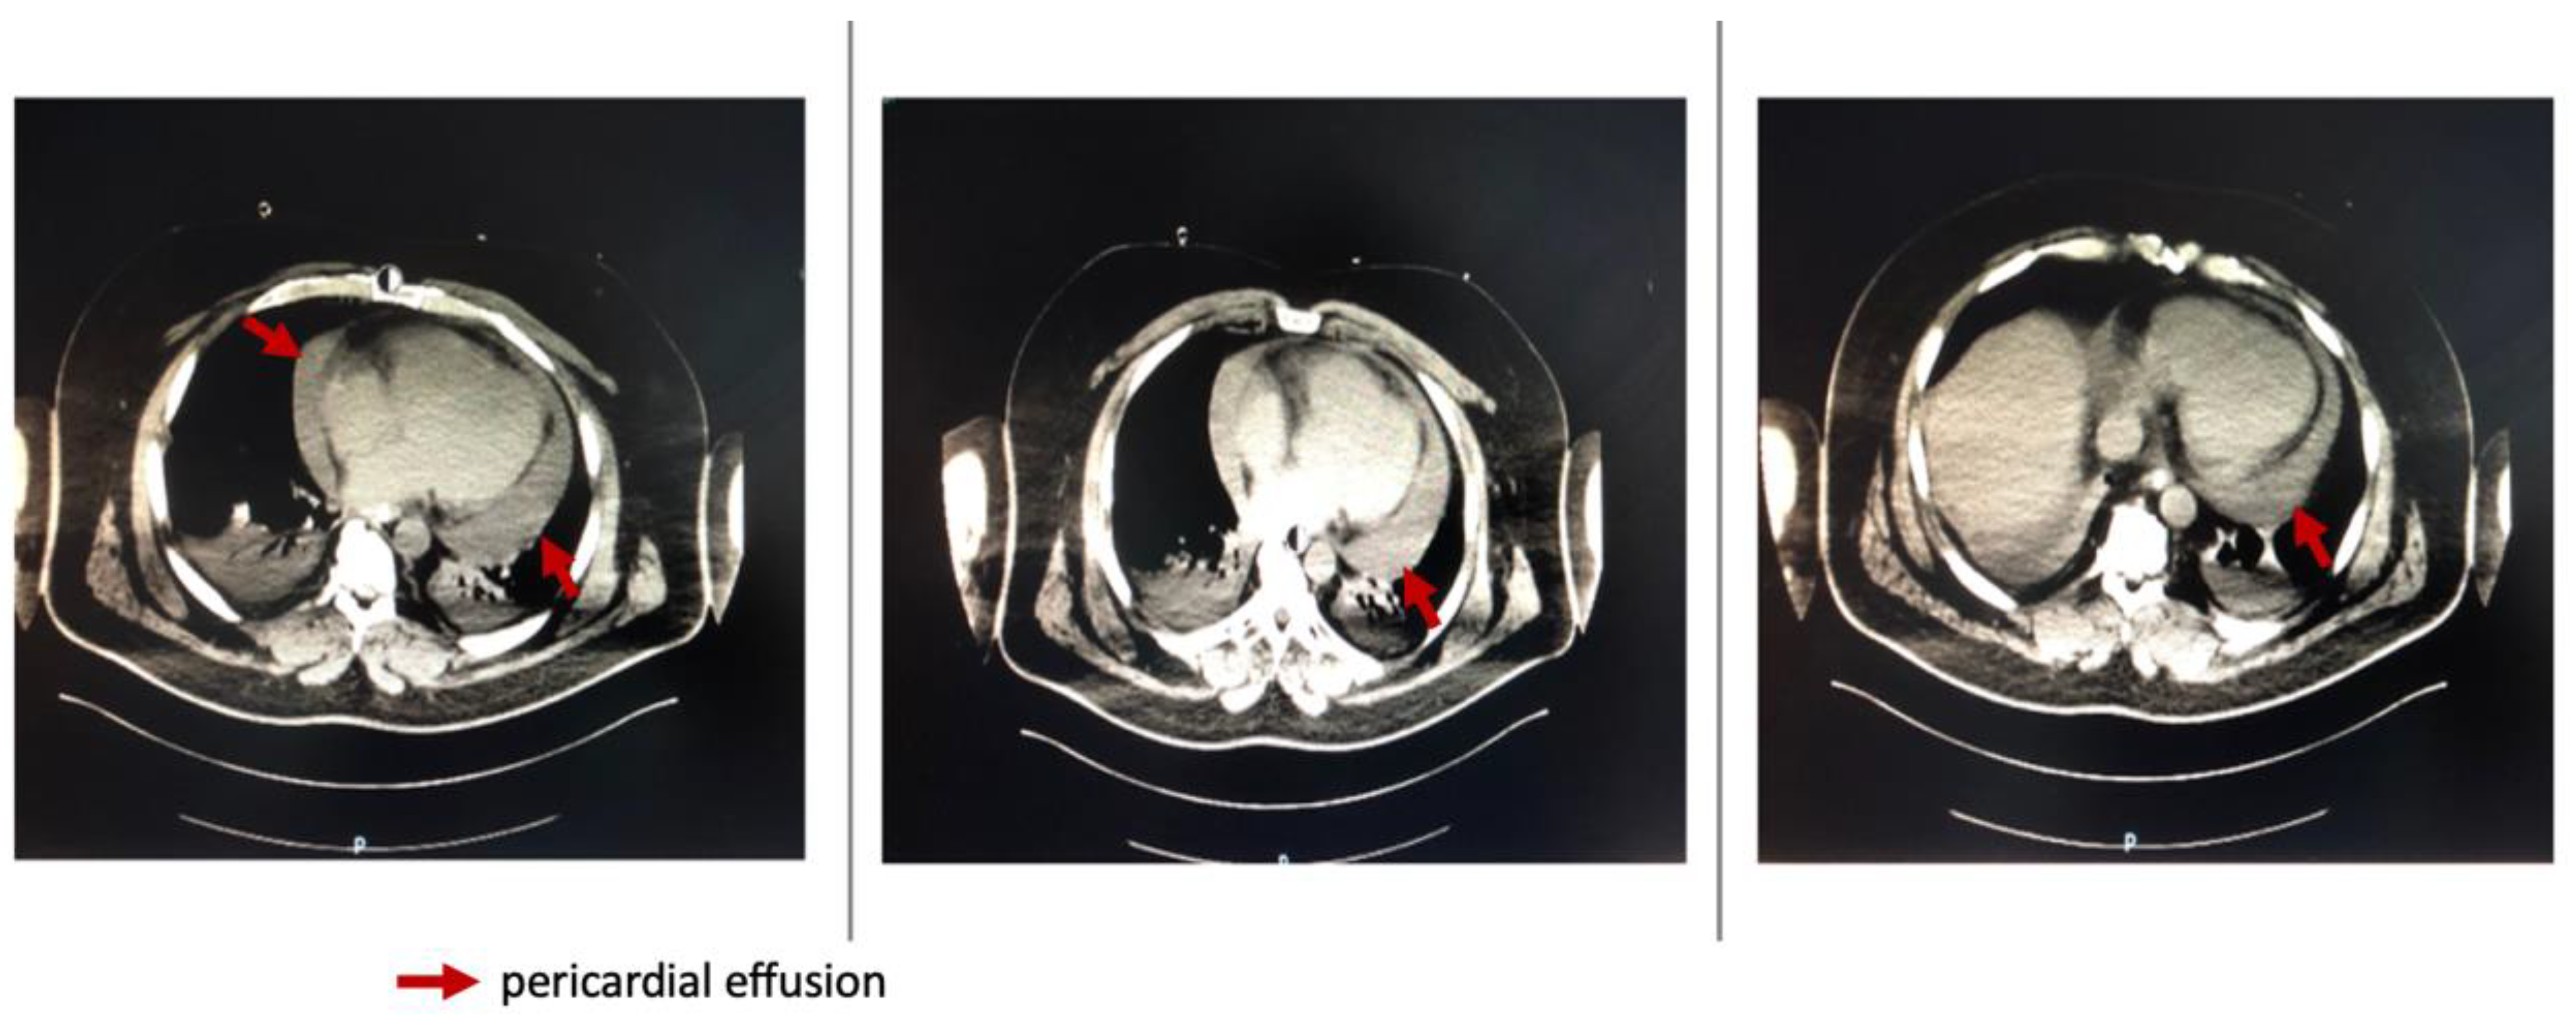

A transesophageal heart ultrasound was promptly performed and confirmed the impressive amount of liquid in the pericardium and right ventricular collapse (Figure 2).

Dynamically performed cardiac ultrasound noted an improvement in the LVEF at 45-50% and minimal pericardial effusion (Figure 3).

Figure 2. Transesophageal heart ultrasound showing pericardial effusion. A—right atrium and right ventricle, B—Left ventricle.

Figure 3. Transthoracic heart ultrasound showing pericardial effusion.